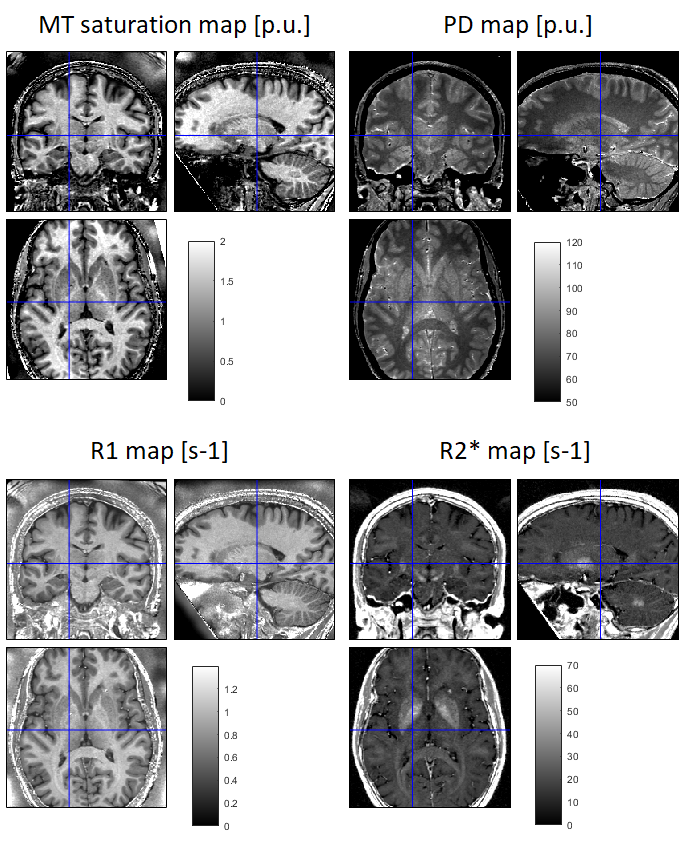

To visualise the maps, it is important to use appropriate windowing range. Typically, the following intensity ranges will provide good rendering:

- PD maps: [50 120] p.u.

- MT saturation maps: [0 2] p.u.

- R2* maps: [0 70] s-1

- R1 maps: [0 1.4] s-1

The following example illustrates typical rendering of the maps (processed from the MPM example dataset,

see tutorial for map creation) as rendered using SPM CheckReg and manual adjustment of the intensity ranges: